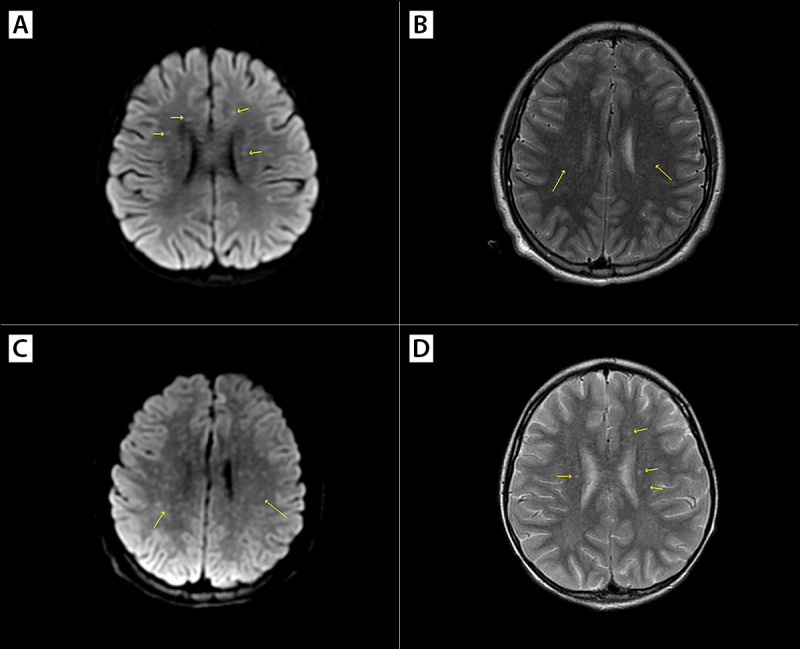

Abstract Image